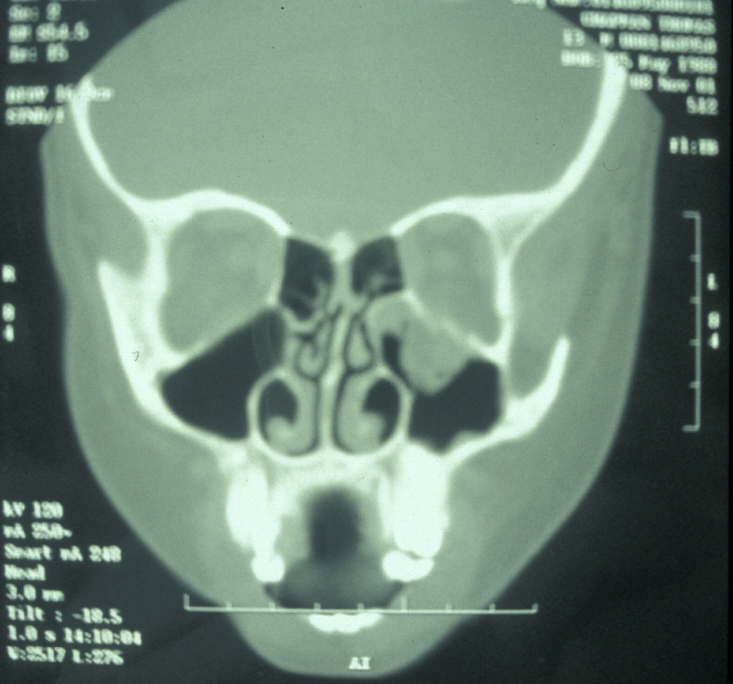

Plain film X-ray radiographs from different angles (occipitomental views) give some information, but a much more accurate assessment of the extent of the fracture can be obtained from CT scans (see Figure 11 for an example).

Figure 11: CT scan of a midface fracture.